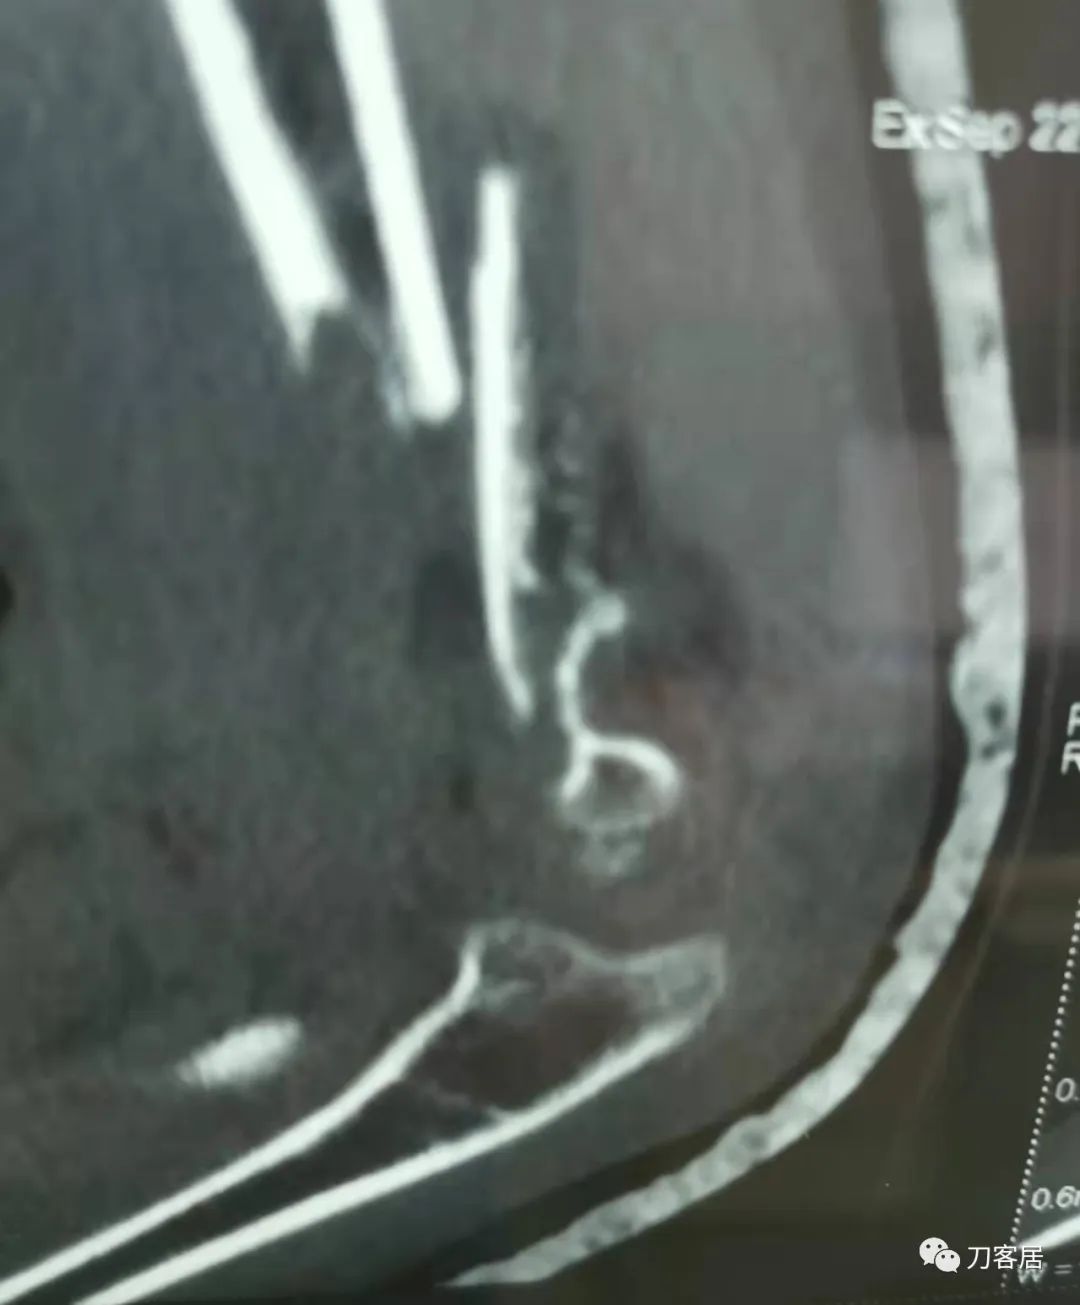

20210921当地县医院CT01

20210921当地县医院CT02

20210921当地县医院CT03

查体:左侧肘关节肿胀明显、疼痛、畸形,局部可见明显青紫瘀斑,左肘关节活动受限,肱骨远端环形压痛(+),局部可及异常活动及骨擦感形成,左上肢末梢桡动脉可触及,左侧腕关节及拇指背伸活动受限,左侧虎口区感觉麻木。辅助检查:自带X线及CT片示:左肱骨髁间粉碎性骨折。

入院诊断:1. 左肱骨髁间粉碎性骨折;2.左肱骨远端骨骺损伤;3. 左桡神经损伤。